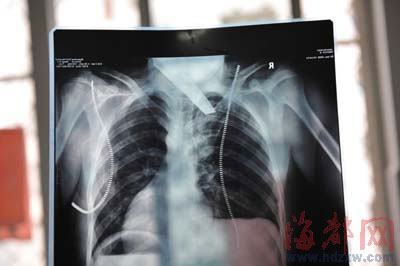

前晚,在第一醫院急救室,經過4個多小時的搶救,醫生將匕首從小勇身上取出,發現這把匕首的刀尖扎斷了1厘米。由于小勇肺部被刺中,昨天上午,醫生再次進行了3個多小時的手術,切除了受傷的部分肺,直到下午,小勇才挺過來!巴α艘灰梗F在總算醒了過來!睏钆恳灰箾]睡,守在手術室外7個多小時,生怕兒子再醒不過來。不過,由于傷勢嚴重,小勇目前戴著氧氣呼吸,仍未脫險。